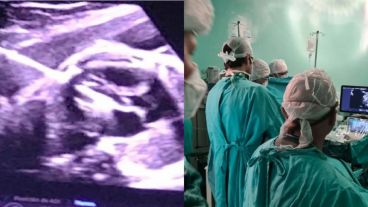

El pasado 18 de diciembre del 2020, operaron a un bebé en el vientre de la madre en Hospital Italiano y la Fundación Hospitalaria, en Buenos Aires. El caso trascendió ahora y los médicos revelaron que se trataba de una paciente oriunda de Rosario.

El feto, de 32 semanas de gestación, fue operado con éxito del corazón y durante la intervención participaron más de 15 profesionales. Los pacientes no tenían cobertura y provenían de un hospital público de La Plata y fueron derivados a la Fundación para este tratamiento.